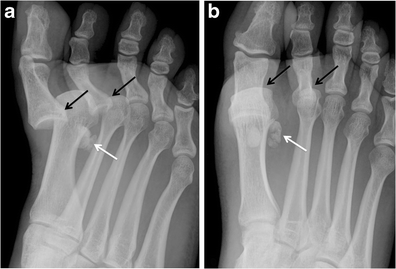

Hallucal sesamoid fracture. Oblique (a) and AP (b) radiographs at the forefoot in a patient after deceleration injury. There are dorsal dislocations of the first and second metatarsophalangeal joints (black arrows), with a comminuted fracture of the lateral hallucal sesamoid (white arrows). Note that the sesamoid fracture pieces would fit together perfectly. The medial hallucal sesamoid is also fractured in this patient